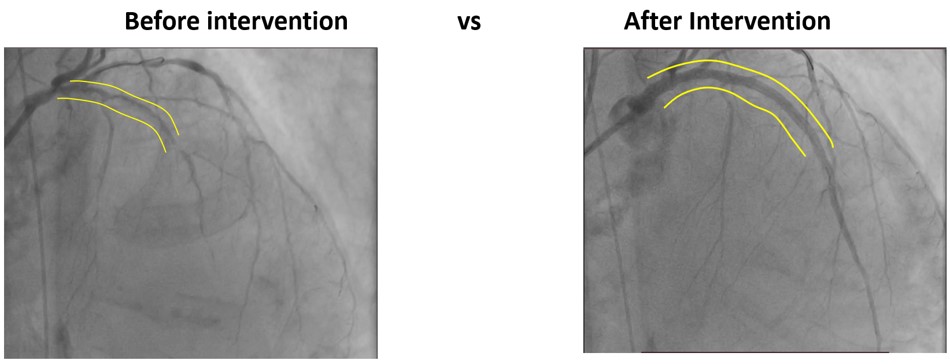

Coronaryangiography revealed diffuse calcified lesion in the LM at bifurcation with 70%stenosis, 99% stenosis at proximal LAD, and 99% stenosis at mid-LAD. Thepatient was diagnosed as CAD, UAP, Heart failure class II NYHA.

Through radial artery access, guiding catheter 1 (7F/EBU3.75) was inserted into the distal LAD. Guidewire 1 (Asahi Sion Blue) and guidewire 2 (Abbott) was unable to reach distal LAD segment and the distal D segment. Balloon 1 (1.0x10 mm, 8 atm) could not pass proximal LAD when sent along the guidewire 1. IVUS of the LAD-LM showed diffuse calcification with >2700 circular arc. Rotational atherectomy was targeted to distal LAD. High-speed rotational atherectomy and low-speed plaque modification was performed on proximal-mid LAD lesions. Then, guidewire 1 (Asahi Sion Blue) was advance to distal LAD. IVUS on LAD-LM revealed circumferential calcification. Intravascular shockwave energy was used to inflate the balloon (3.0 x 12 mm shockwave balloon) at 4-6 atm and then IVUS showed a rupture of deep LAD calcified ring. Then, the distal LAD was predilated [Balloon 2 (1.5x20 mm, 6-12 atm), balloon 3 (2.0x20mm, 6-12 atm), balloon 4 (2.0x20 mm, 6-12 atm) and balloon 5 (NC balloon 2.0x20 mm, 20 atm)]. Stent 1 (DES 2.25x23 mm, 9 atm), stent 2 (DES 2.75x30 mm, 9 atm), stent 3 (DES 3.00x30 mm, 9 atm), stent 4 (DES 3.50x 28mm, 9 atm) was planted on the mid LM-LAD segment and then balloon 6-10 (PTCA ballon 2.75 x12mm, 14-28 atm); (PTCA ballon 3.00x 12mm, 14-28 atm); (PTCA ballon 3.00x15 mm, 14-28 atm); (NC balloon 3.00 mm x 15 mm, 14-28 atm); (coronary mastoid 3.00x15 mm , 14-28 atm) was planted for post dillatation. Post procedural IVUS showed satisfactory result.

Complex calcified LAD lesions can be successfully treated with combined Rotational atherectomy with intravenous lithotripsy (IVL) to manipulate the heavily calcified lesion. Ensuring optimal stent expansion can lead to long-term procedural success.